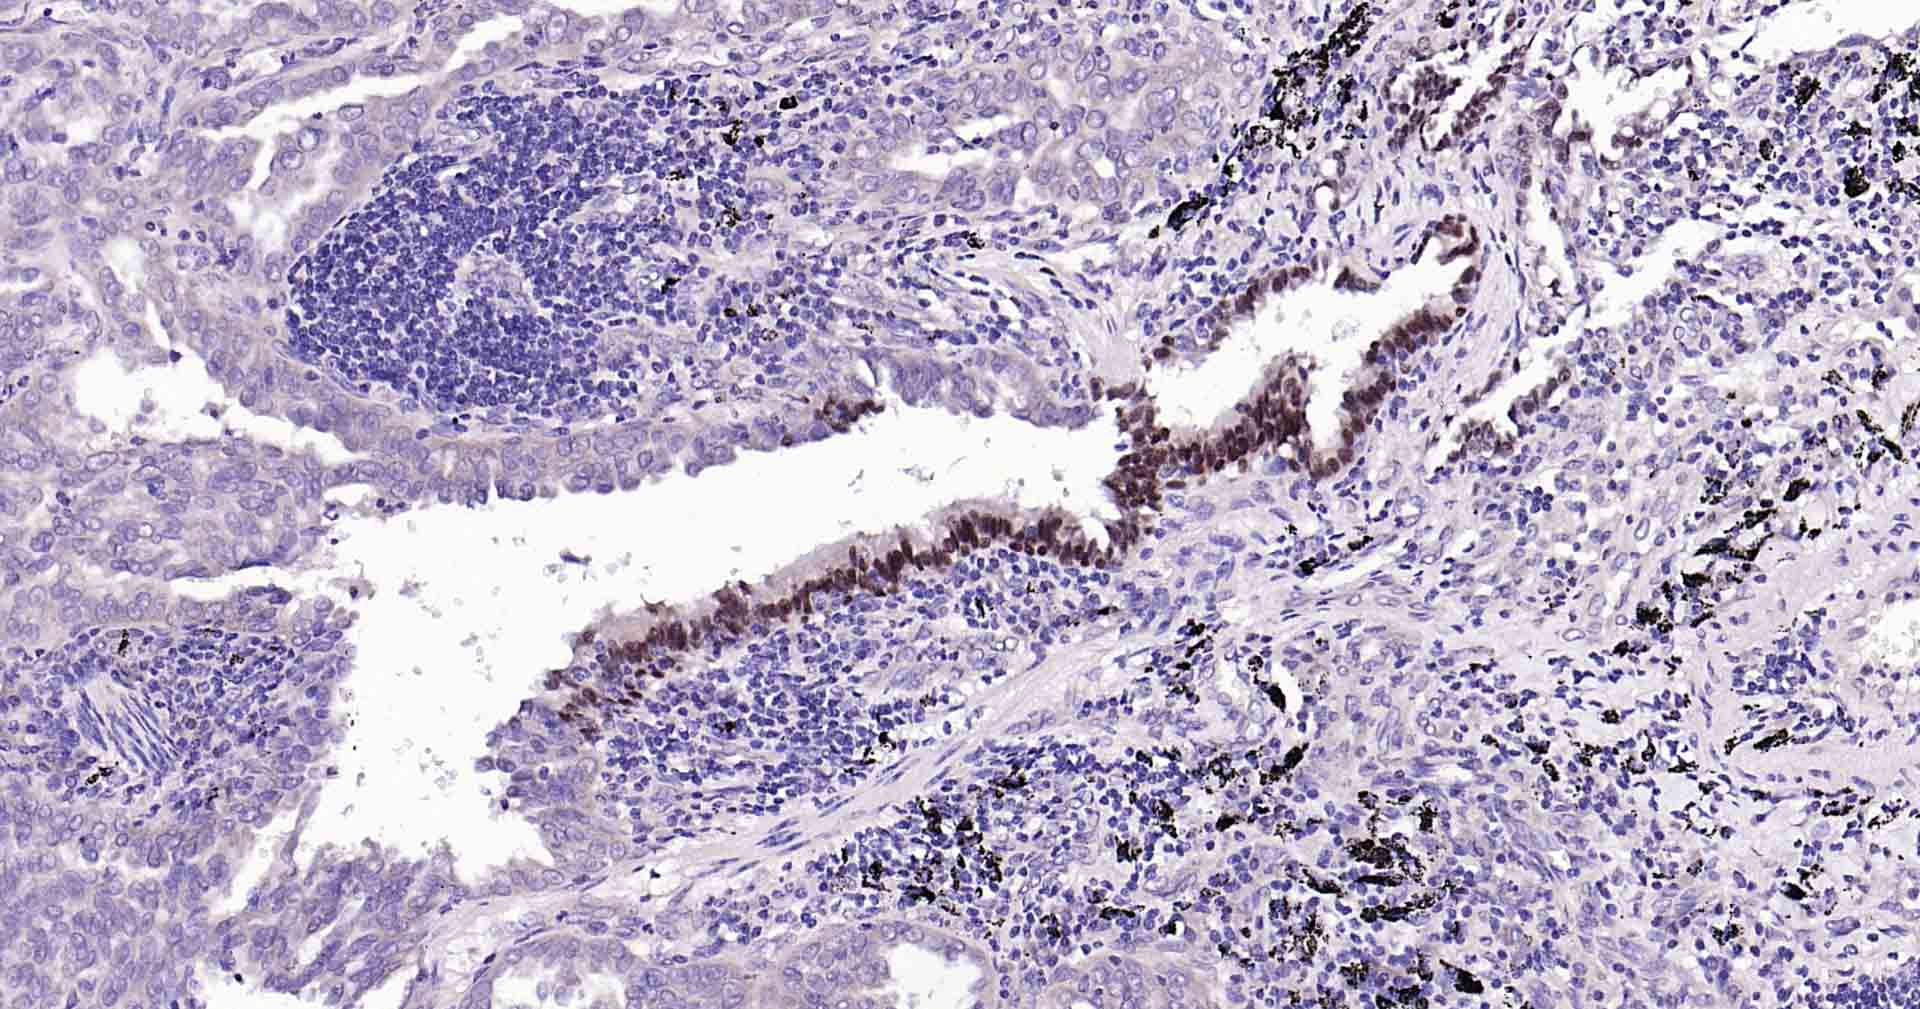

Paraformaldehyde-fixed, paraffin embedded Human Glioma; Antigen retrieval by boiling in sodium citrate buffer (pH6.0) for 15 min; Antibody incubation with SOX2 Monoclonal Antibody, Unconjugated(bsm-60788R) at 1:300 overnight at 4°C, followed by conjugation to the SP Kit (Rabbit, SP-0023) and DAB (C-0010) staining.